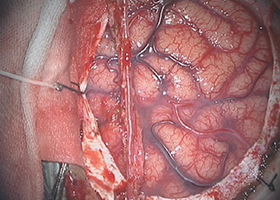

てんかんの治療は抗てんかん薬などの薬での治療が中心ですが、薬物治療で発作の抑制が困難な難治性てんかんに対しては、様々の検査を行い、てんかん焦点を同定して外科的に切除する治療があります。この治療により、抗てんかん薬の減量が可能になることや、てんかんの回数を減らす効果が期待されます。また、てんかん焦点の特定が困難な場合や、てんかん焦点が脳の運動や言語など、重要な機能に関連する領域にある場合は、手術により、脳表に電極を留置し、脳表から直接脳波を記録したり、電気刺激したりすることによって、てんかん焦点を同定しつつ、切除できるかどうかを検討することがあります。切除が困難な症例でも、迷走神経刺激療法という手術で治療可能な場合があります。この治療は、首の左側にある迷走神経に電極を巻き付け、電気刺激を行うことによって、てんかん発作の頻度や程度を軽くする治療です。

-

後頭葉てんかんの手術例です。 -

左:開頭して、脳の表面に電極を置きます。

中:脳表の電極から脳波を記録し、

てんかん焦点を同定します。

右:てんかん焦点を切除することで、

発作のコントロールが可能です。